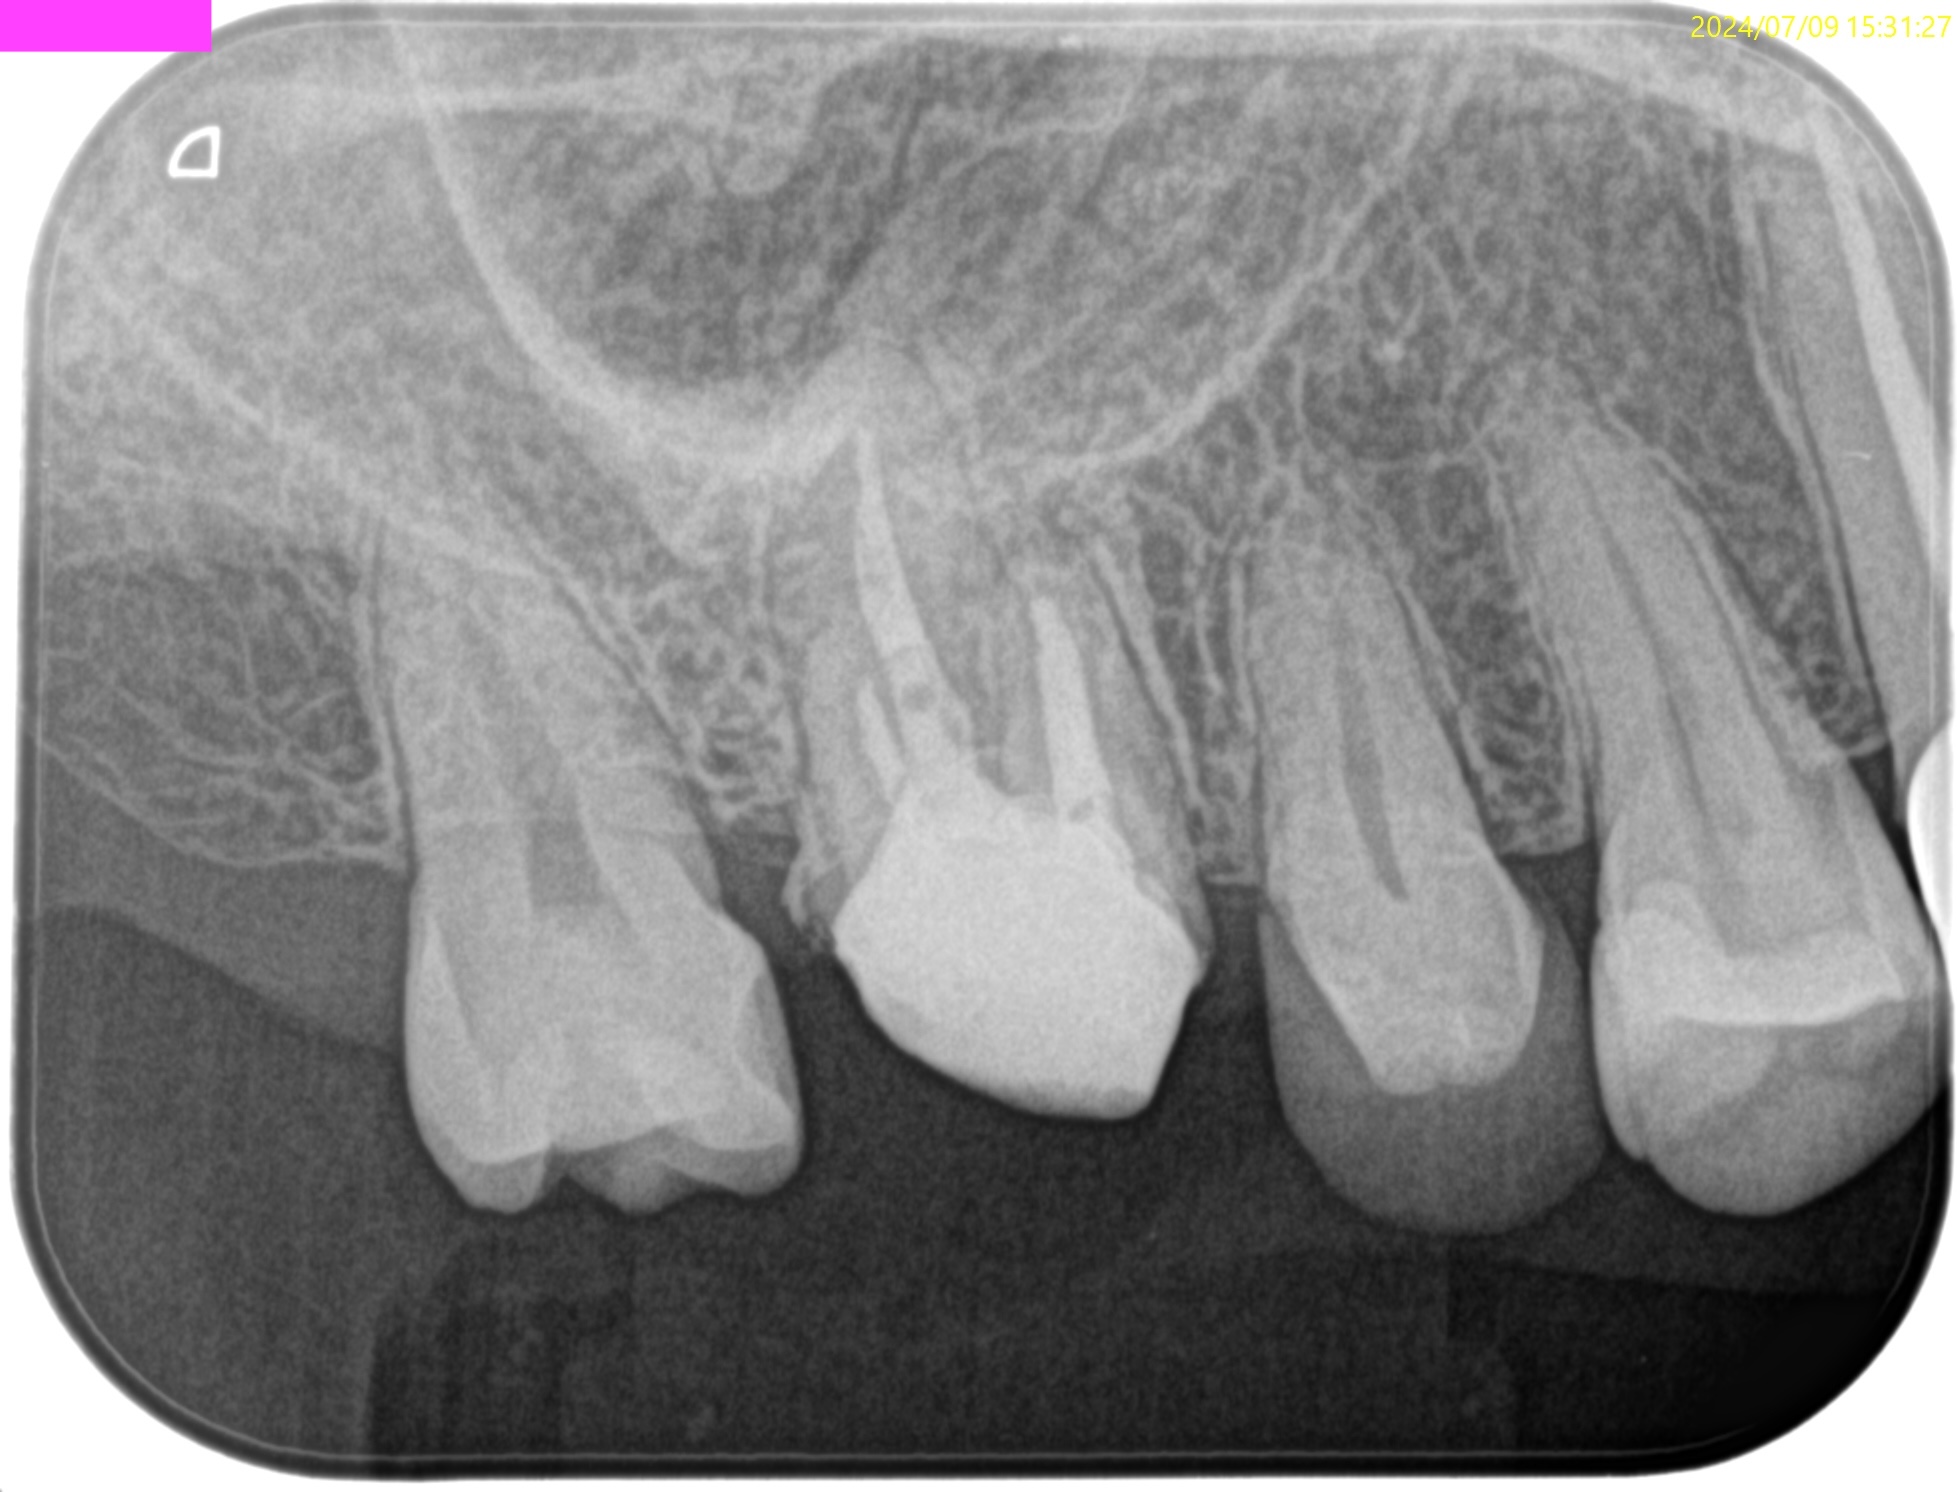

術後にPA, CBCTを撮影した。

#3

MB

DB

P

#14

#16

再治療では3根管とも#25.VがいきなりReference Pointに到達したことから#60.02まで形成した。

作業内容は以下だ。

#3 作業長 #14 作業長 #16 作業長#3,14は#60.02まで、

#16に至っては根管形成自体ができていない。洗浄のみで再根管治療が終了している。気休めに超音波洗浄しただけだ。

こんなことで治癒するのだろうか?